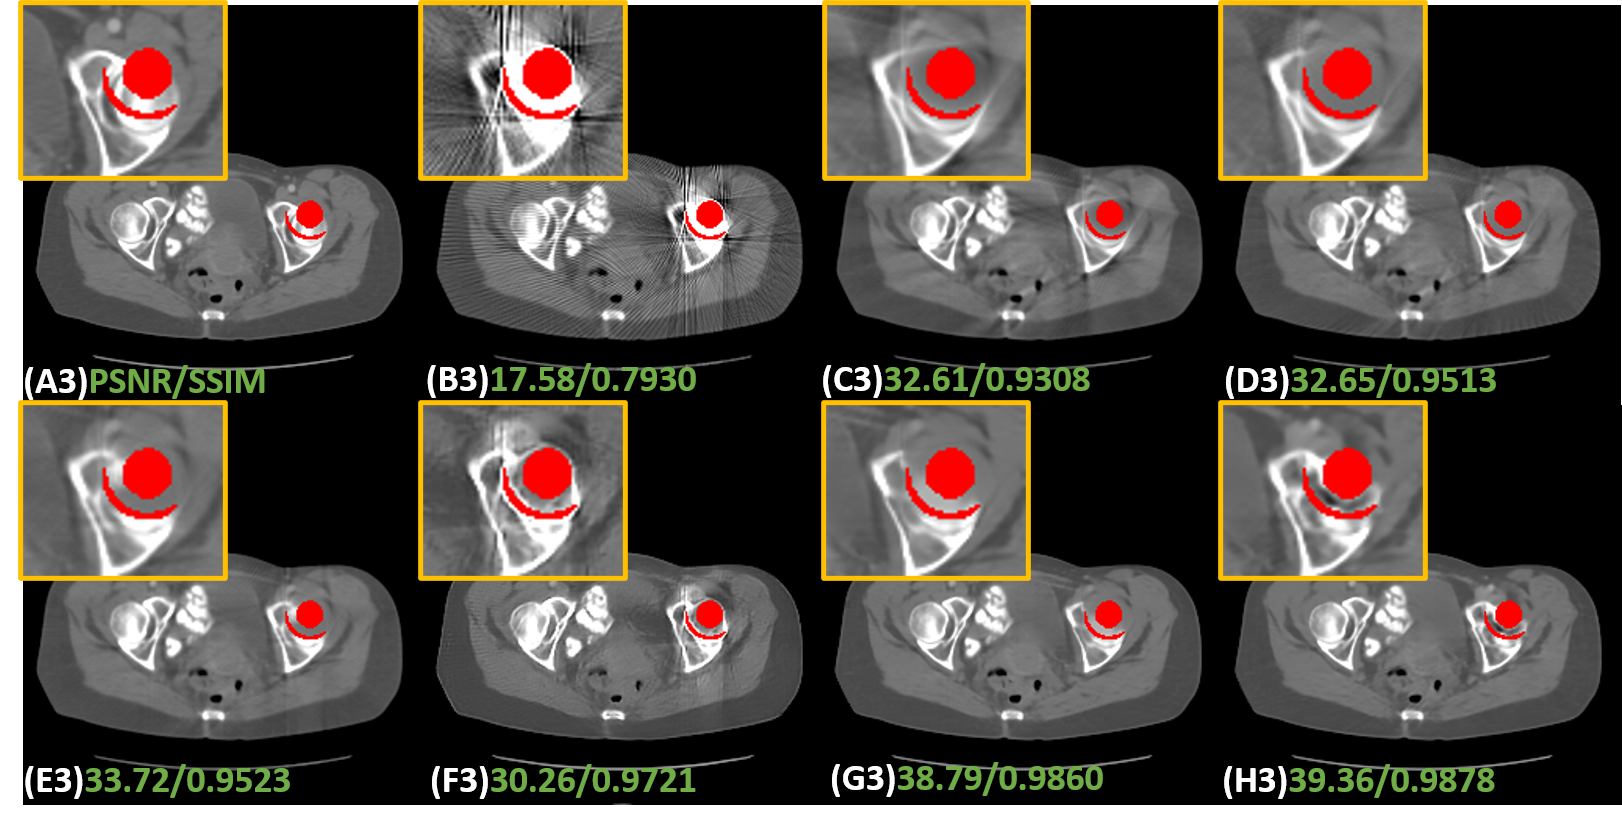

1) Effectiveness of prior estimation. Most dual-domain MAR methods usually use original or LI-interpolated sinogram and corresponding reconstructed CT images as inputs, or adopted LI’s corrected results as inputs. However, the first case results in incomplete artifact reduction and maintains some obvious artifacts in final corrected images. In addition, since LI is just a rough estimation, which gives rise to details lost around the metal. A possible solution is to generate both good quality prior sinogram and image. To investigate the effectiveness of the prior image and sinogram generated by our proposed disentanglement module, a network without this module, termed Refine-Net, is trained and we take metal-affected CT image and sinogram as inputs. Table 2 shows the quantitative results. It is clear to see that aided by prior image and sinogram, our model achieves much better score in terms of both metrics. As shown in In Fig. 8 (B), there are obvious artifacts indicated by a blue arrow.

2) Effectiveness of . There are two ways to obtain high quality prior image and sinogram. One is just predicting the clean data directly from contaminated data. The other is learning residual part and get the clean part by subtracting the learned residual data from original corrupted data. However, these methods may fail to separate the clean data or residuals from original data completely. In other words, there could be some useful information remaining in the restored data or residuals. To tackle this problem, inspired by disentangling representation, we learn both clean part and residual part simultaneously. In addition, we adopt to produce a lossless decomposition. To investigate the effectiveness of , we trained two networks, Clean-IDOL and Art-IDOL, without . It can be seen in Table 2 that both Clean-IDOL and Art-IDOL achieve lower SSIM and PSNR values than IDOL-Net. In Fig. 8, Clean-IDOL introduced secondary artifacts indicated by green arrow. Art-IDOL shows slight anatomic structure distortion marked by yellow dotted box. It is noticeable that the result of IDOL-Net is most consistent with the referenced image in all the methods.

3) Effectiveness of parallel branches. To show the effectiveness of our proposed interactive dual-domain parallel branches, we trained two networks, dubbed Prior-Im and Prior-Sino, which are only with image domain branch or sinogram domain branch, respectively. It can be seen in Table 2 that Prior-Sino gains lower SSIM and PSNR scores than other methods. The possible reason lies in that Prior-Sino restored projection data within metal trace region using the original contaminated data and the distortion introduced by inaccurate result will expand to the whole reconstructed image, which heavily lower both quantitative scores calculated in image domain. Prior-Im significantly improves the qualitative and quantitative results compared to Prior-Sino, but as shown in Table 2 and Fig. 8, our IDOL-Net have superior performance to Prior-Im, which provides impressive support for our claim that the proposed interactive dual-domain parallel branches are efficient.